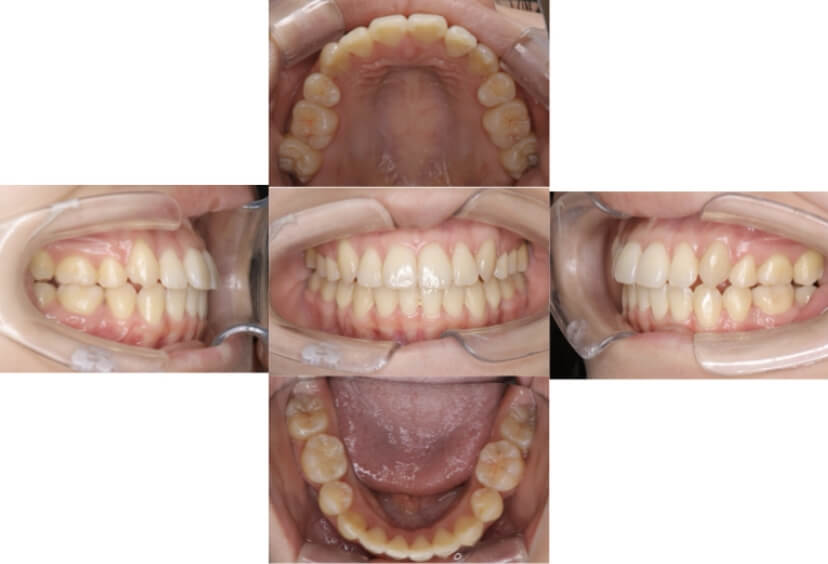

上下顎叢生(上下の前歯のガタガタ)のケースです。

装置はラビアル(上下表側)で、上下顎の小臼歯を4本抜歯を行っています。抜歯したスペースを使って、上下の前歯の後方移動と叢生(ガタガタ)の改善を行っています。

主訴 歯並びが悪く、舌を噛んでしまうのを治したい。

年齢・性別 27歳 男性

お住まいの地域 東京都大田区

治療方針 抜歯スペースを利用して上下前歯の叢生(ガタガタ)の改善

抜歯部位 上下顎左右第一小臼歯

使用装置 ラビアル(上下表側)、顎間ゴム

治療期間 3年1か月

治療回数 30回

AFTER